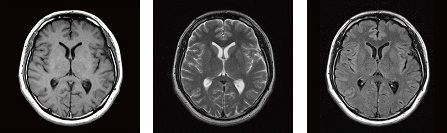

大脳皮質下に嚢胞性病変が集簇してみられるMVNTとは?MRI画像所見のポイント, SENDA/BPAN | オートファジー病(SENDA/BPAN・Vici症候群),

SENDA/BPAN | オートファジー病(SENDA/BPAN・Vici症候群), MRIとは | 医療法人 翠清会梶川病院 【脳神経疾患専門病院】,